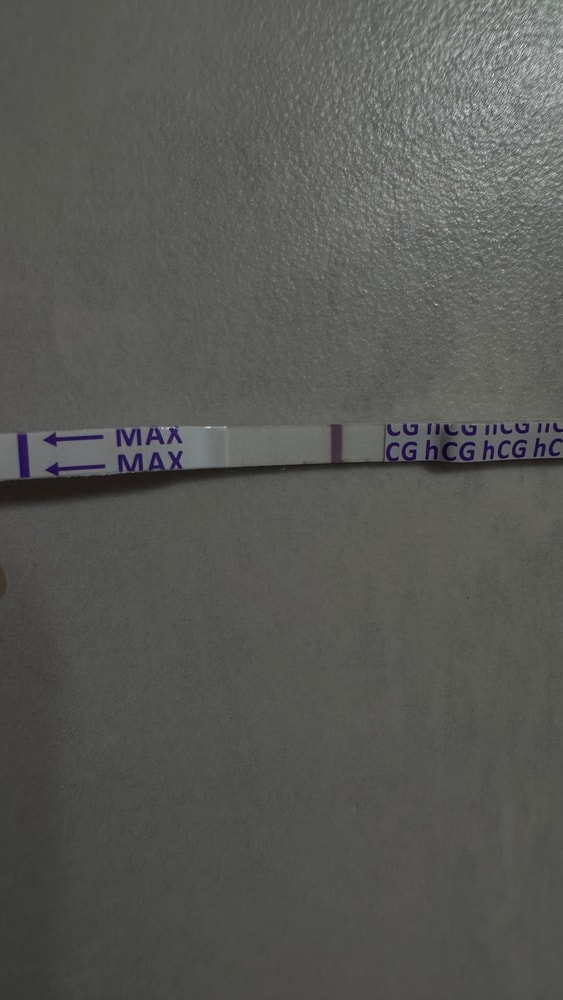

Собрала тесты с цикла в коробку, как всегда😩

Вышла из дисперсии очередной неудачи…заказала тесты, уже в пути…ведь тестов много не бывает, уж я то знаю, спустя столько л

Тесты в студию🤗

Что-то я понять не могу, свой организм вместе с тестами на овуляцию.

понедельник вечер:

Вторник 7 утра:

Тестик на овуляцию ярчает) я радуюсь как ребенок😂 овуляция с СПКЯ, большая редкость. Последняя была в январе (стимулированная), а предпоследняя в мае 2024 года. 20 д.ц и счаст